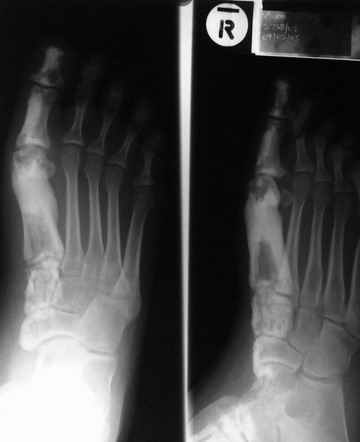

Наконец, важным внешним клиническим выражением мелореостоза могут служить деформативные явления, из которых

раньше всего бросаются в глаза осевые уклонения в сторону одного из пальцев кисти.

врачи не обращаются за консультативной помощью к рентгенологам. Точное распознавание мелореостоза возможно

исключительно и на основании рентгенограмм при условии знакомства с причудливой рентгенологической картиной

мелореостоза. Здесь обязательно требование подвергать ренттенологическому исследованию скелет и во всяком случае

конечность в целом, а не только ограниченный участок костно-суставной системы, на котором сосредоточено внимание

больного и лечащего врача.

Таким образом, в типичных случаях мелореостоза вряд ли может возникнуть трудность

диференциально-диагностического порядка. В высшей степени характерная рентгенологическая картина имеет решающее

не только устанавливающее, но и дифе- ренциально-диагностическое значение. Ошибки происходят лишь в результате